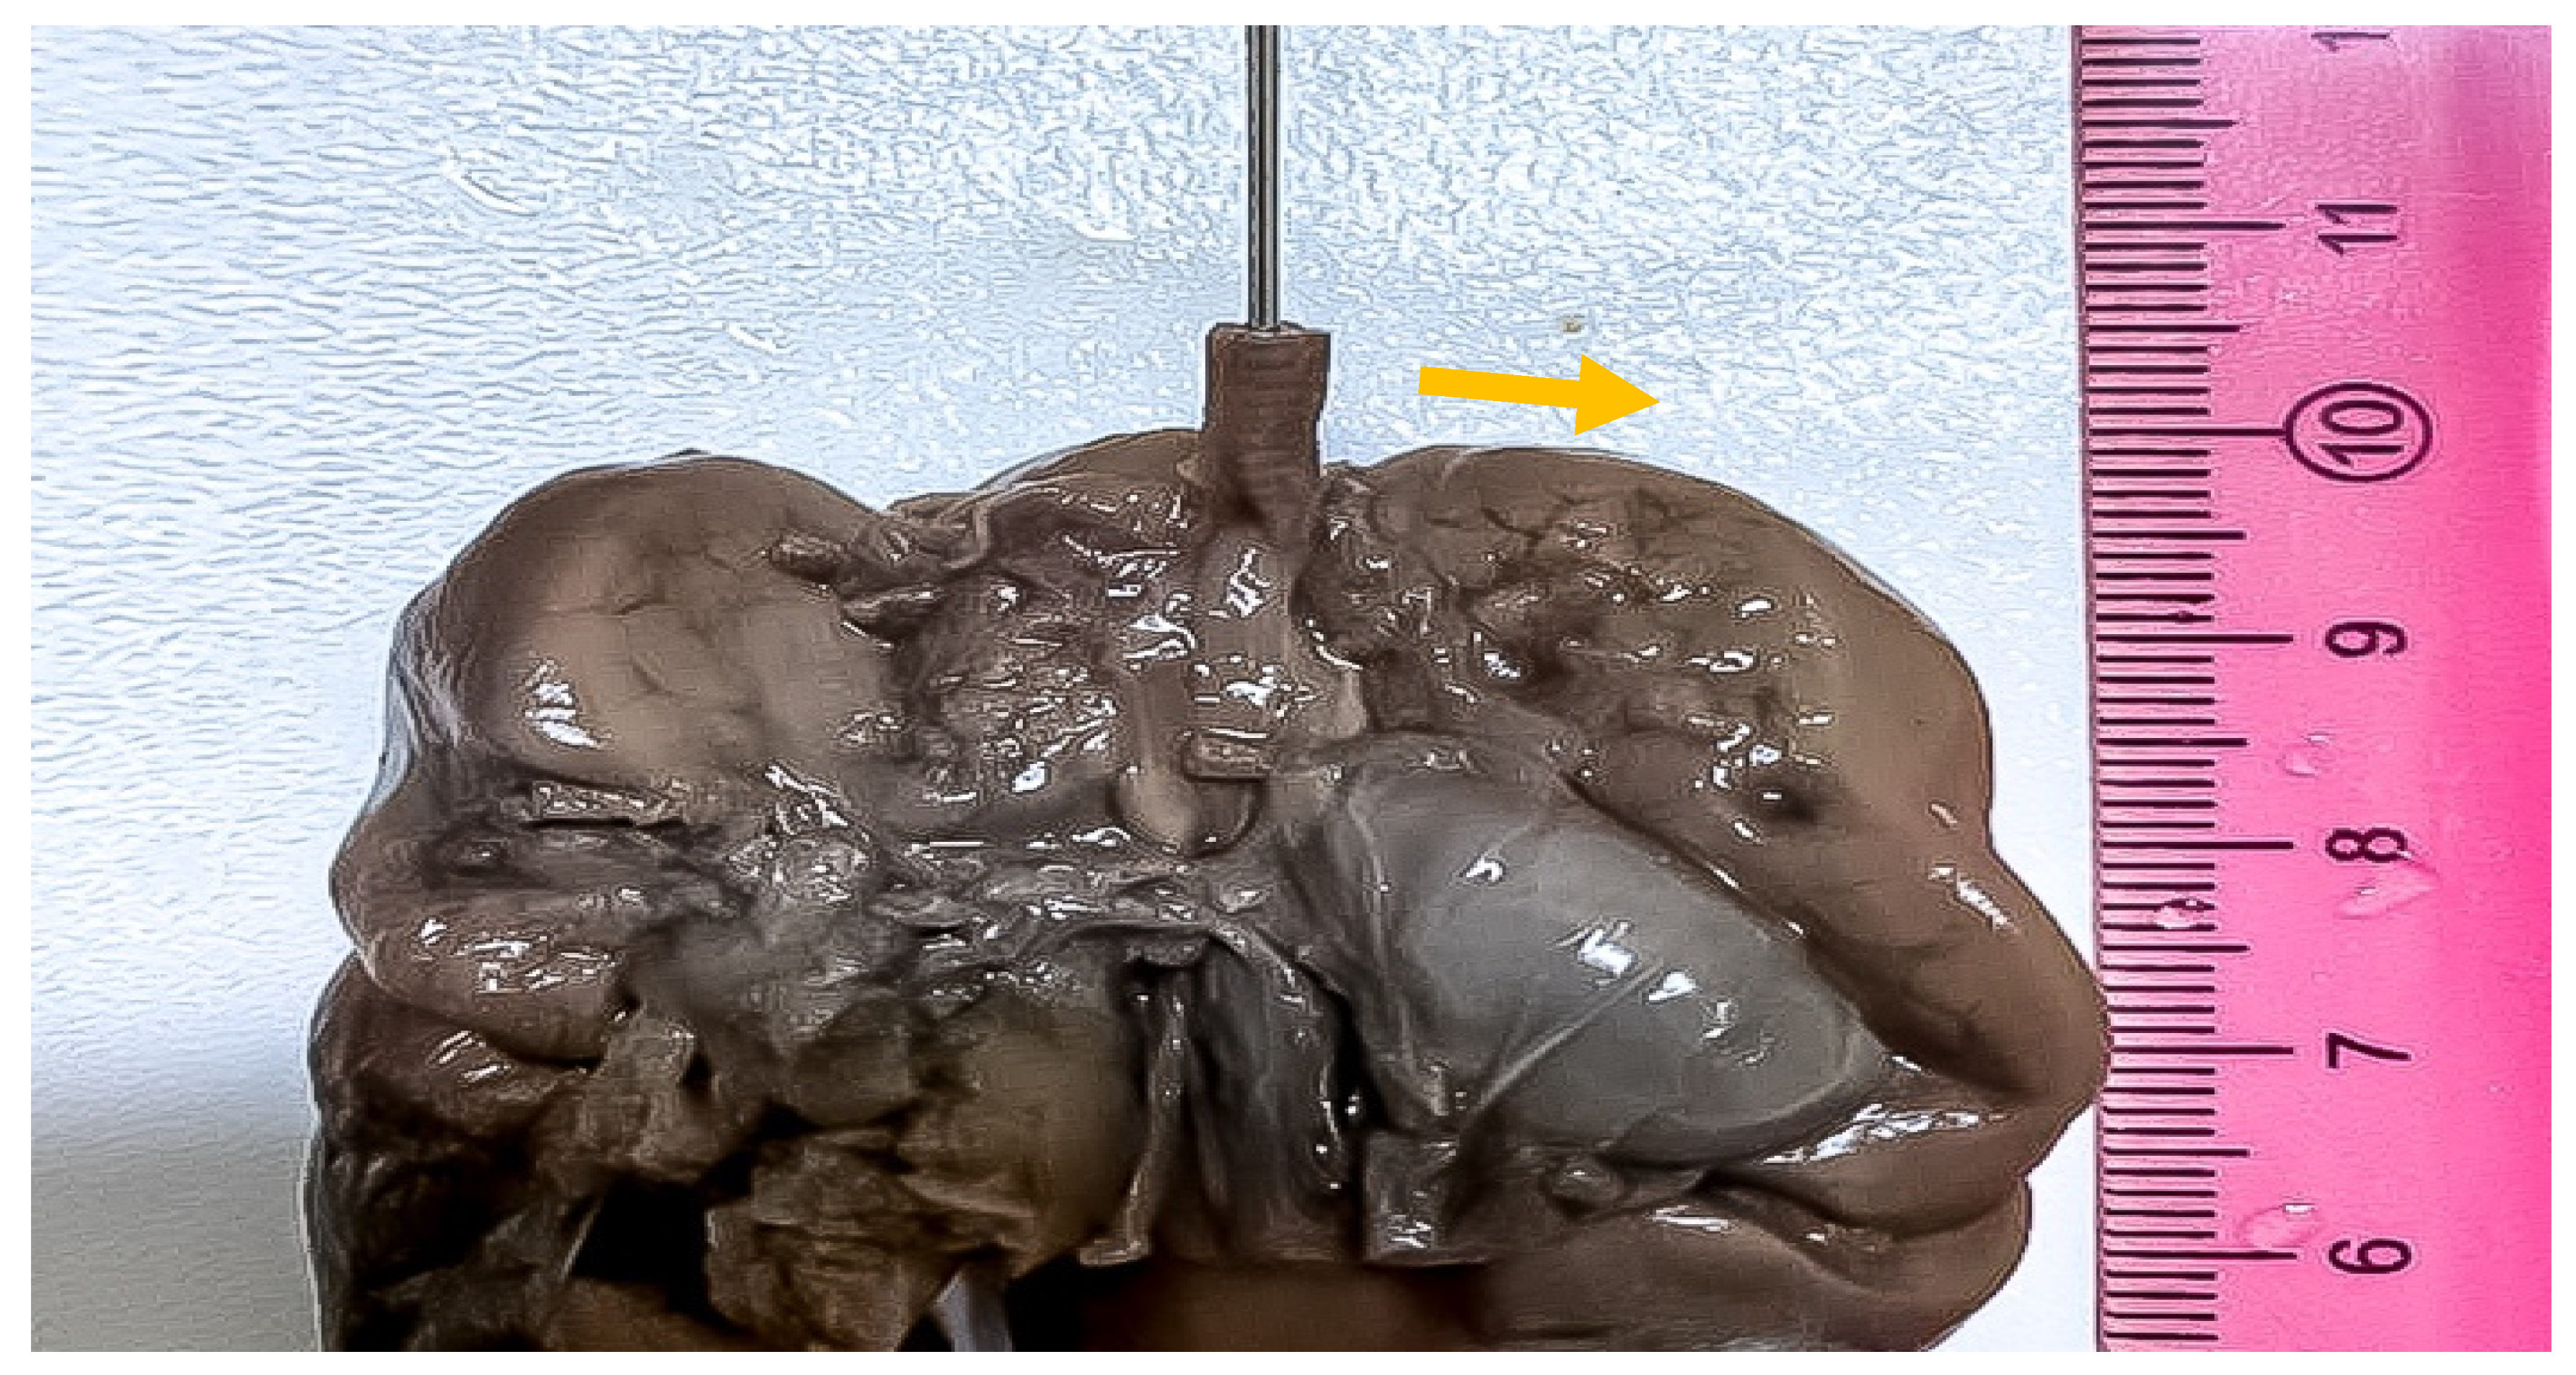

2. Case Report